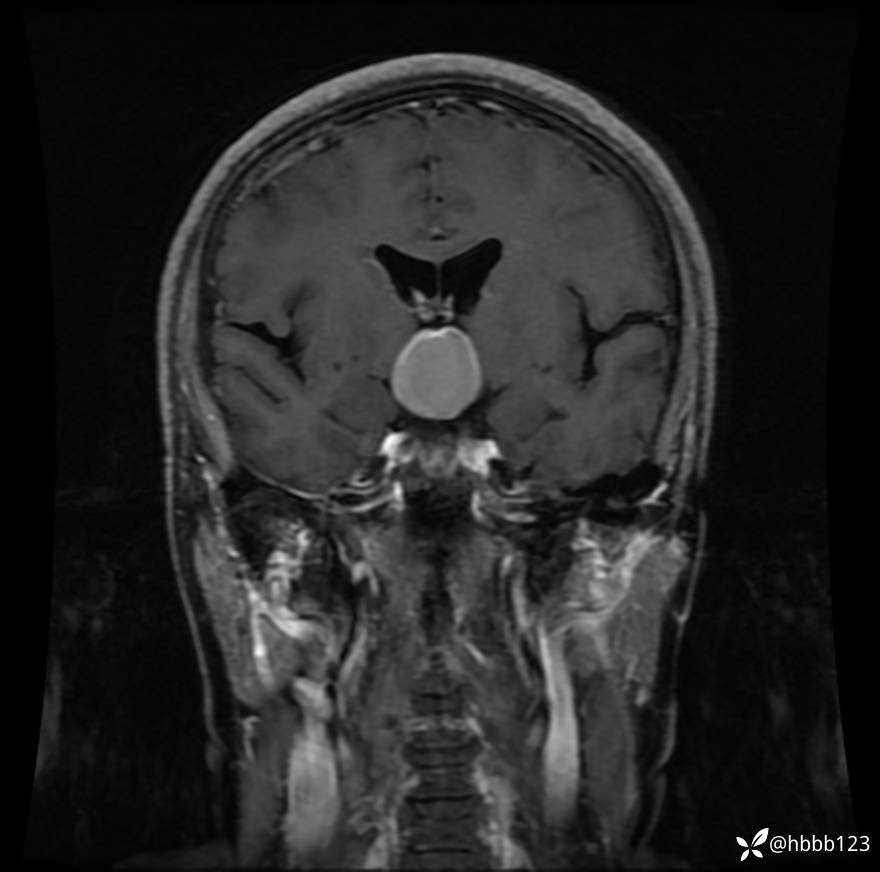

颅脑MRI平扫+增强扫描:

T1WI 增强 冠状位重建: